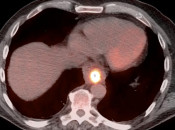

- The Heterogeneous Liver

- Liver Ablation

- Hypermetabolic Geographic Fatty Infiltration

- Hypermetabolic Hepatic Adenoma